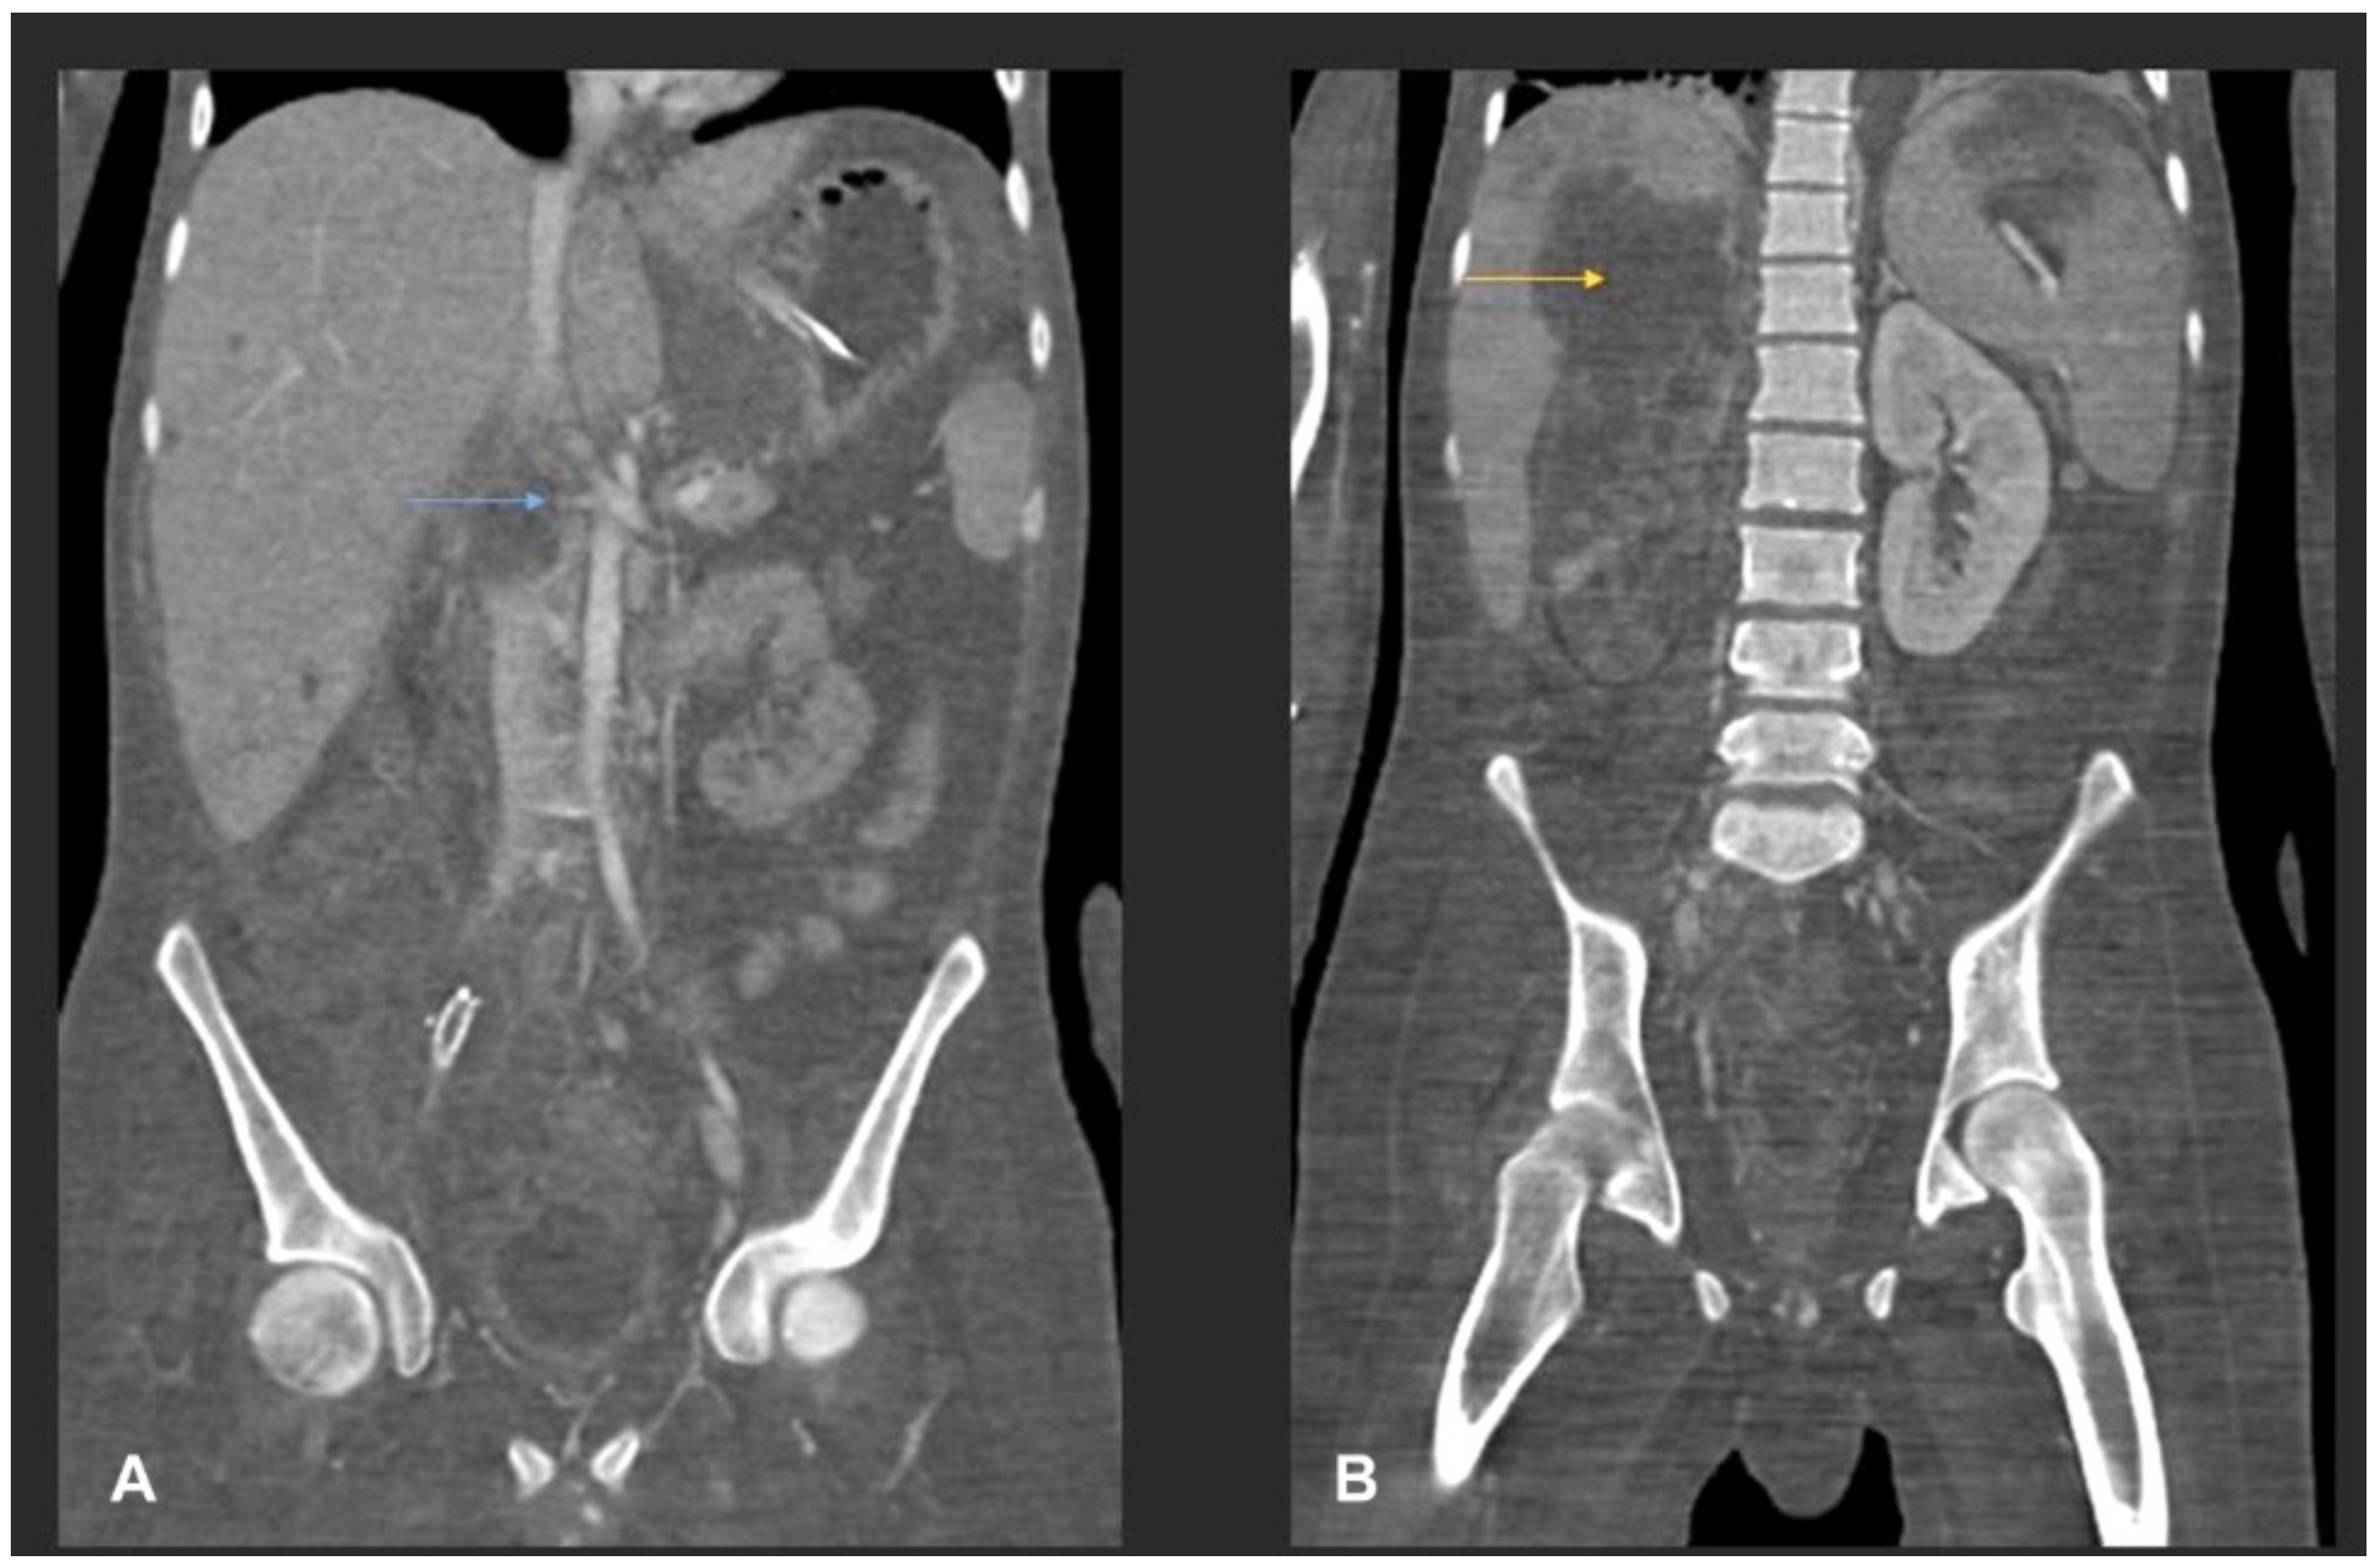

Despite the aforementioned surgical interventions and optimisation of antifungal therapy, including the empiric addition of isavuconazole (with continuation of high-dose liposomal amphotericin), the disease continued to show fulminant progression, resulting in extensive angioinvasion with involvement of the right common iliac artery, the left infrapopliteal artery and the right renal artery (Figure 4), finally resulting in bilateral lower limb ischemia and infarction of the right kidney (Figure 5).

Figure 4.

(A) MIP coronal CT angiography of aorta and lower limb shows a segmental narrowing and luminal irregularities of right external iliac artery (blue arrow). No occlusion. Distal run off was satisfactory. Rest of the lower limb vessels were patent and normal (not shown). (B) MIP coronal image of the aorta and lower limbs shows cut-off of the proximal right common iliac artery suggestive of thrombotic occlusion (yellow arrow). A stent is seen in the right external iliac artery (red arrow). Right iliac fossa shows extensive inflammatory phlegmonous mass-like soft tissue thickening.